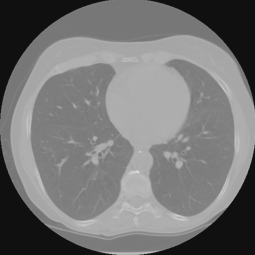

We demonstrate the performance of our proposed network on two datasets: lung CT datasets(fig 9) from Data Science Bowl 2017 for supervised training and test, and

Zubal’s phantom CT data (fig 9) from neck to mid-thigh, except lung position, for test the ability of unsupervised transfer learning. The lung CT train set is with 6312 images (from 38 persons) and test set is with 113 images(from 2 persons). The Zubal’s unsupervised test set is 40 images of 1 person.

Refer to caption

Figure 9: The inpainted sinogram and reconstructed images for test datasets of lung CT from Data Science Bowl 2017. We compair three reconstrucion methods: FBP, our proposed supervised-trained network, and iterative SART reconstrucion with TV regularization. Both the proposed network and SART-TV method reduce the streaking artifacts. And our results have less cartoon-like artifacts than SART-TV. The display window is [-1, 1].

Fig 9 and Table I demonstrate the experiment results for the lung CT data. Both the proposed network and SART-TV method reduce the streaking artifacts caused by the sinogram inconsistencies in angle, while SART-TV introduced piecewise constant cartoon-like artifacts because of the TV normalization. The quantitative studies indicate the superiority of the proposed method in terms of absolute error and structural.

TABLE I: Quantitative Comparsion for FBP, SART-TV and Proposed Method for Lung CT test dataset (113 images)

FBP SART-TV Proposed

avg. PSNR(dB) 22.51 25.23 33.86

avg. SSIM 0.9249 0.9088 0.9781